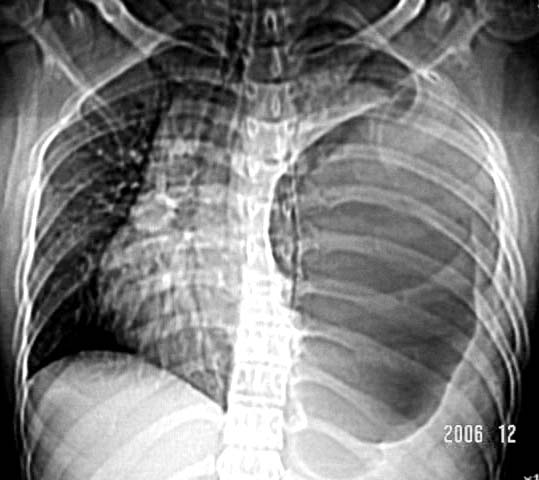

标题: CT5517:女性、24岁,反复胸痛、气促不能平卧半月。 [打印本页]

标题: CT5517:女性、24岁,反复胸痛、气促不能平卧半月。

左肺可见二个含气或液气的囊状影,左肺段支气管、左肺动脉显示不清,纵隔右移,考虑:左肺支气管肺囊肿,左肺发育不良,纵隔疝。

左侧气液腔与胃腔影相连,考虑膈疝。钡餐检查有助于诊断。

我看这是膈疝,在纵隔窗第六\\七幅图像上可见胃粘膜影,再者可见两个腔影,这在液气胸是不会有的.

“反复胸痛、气促不能平卧半月”。+影像学表现=膈疝